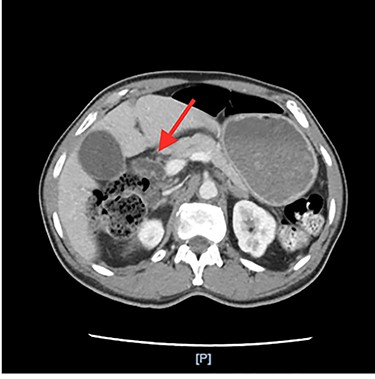

He had an ultrasound (US) and CT abdomen/pelvis showing abnormal intra and extra hepatic biliary ductal dilatation, suspicious for obstruction (Figs. 1 and 2). He then had an MRCP showing ductal dilation with no obvious filling defect. The total bilirubin, direct bilirubin and lipase was normal at 0.4 miligrams per deciliter (mg/dl), 0.1 mg/dl and 38 units per liter (unit/L), respectively. Liver function tests were within normal limits.

Annular pancreas encircling the pylorus and the first and section portions of the duodenum.

After the MRCP, the patient had an episode of hematemesis with a hemoglobin drop to 7.9 grams/deciliter (g/dl) from 11.9 g/dl. Gastroenterology performed an upper endoscopy and endoscopic ultrasound showing gastritis but no ulcers and severe stenosis of the pylorus which could not be traversed with an adult or pediatric scope. Extensive discussion with the radiology and gastroenterology led to a differential diagnosis of annular pancreas.